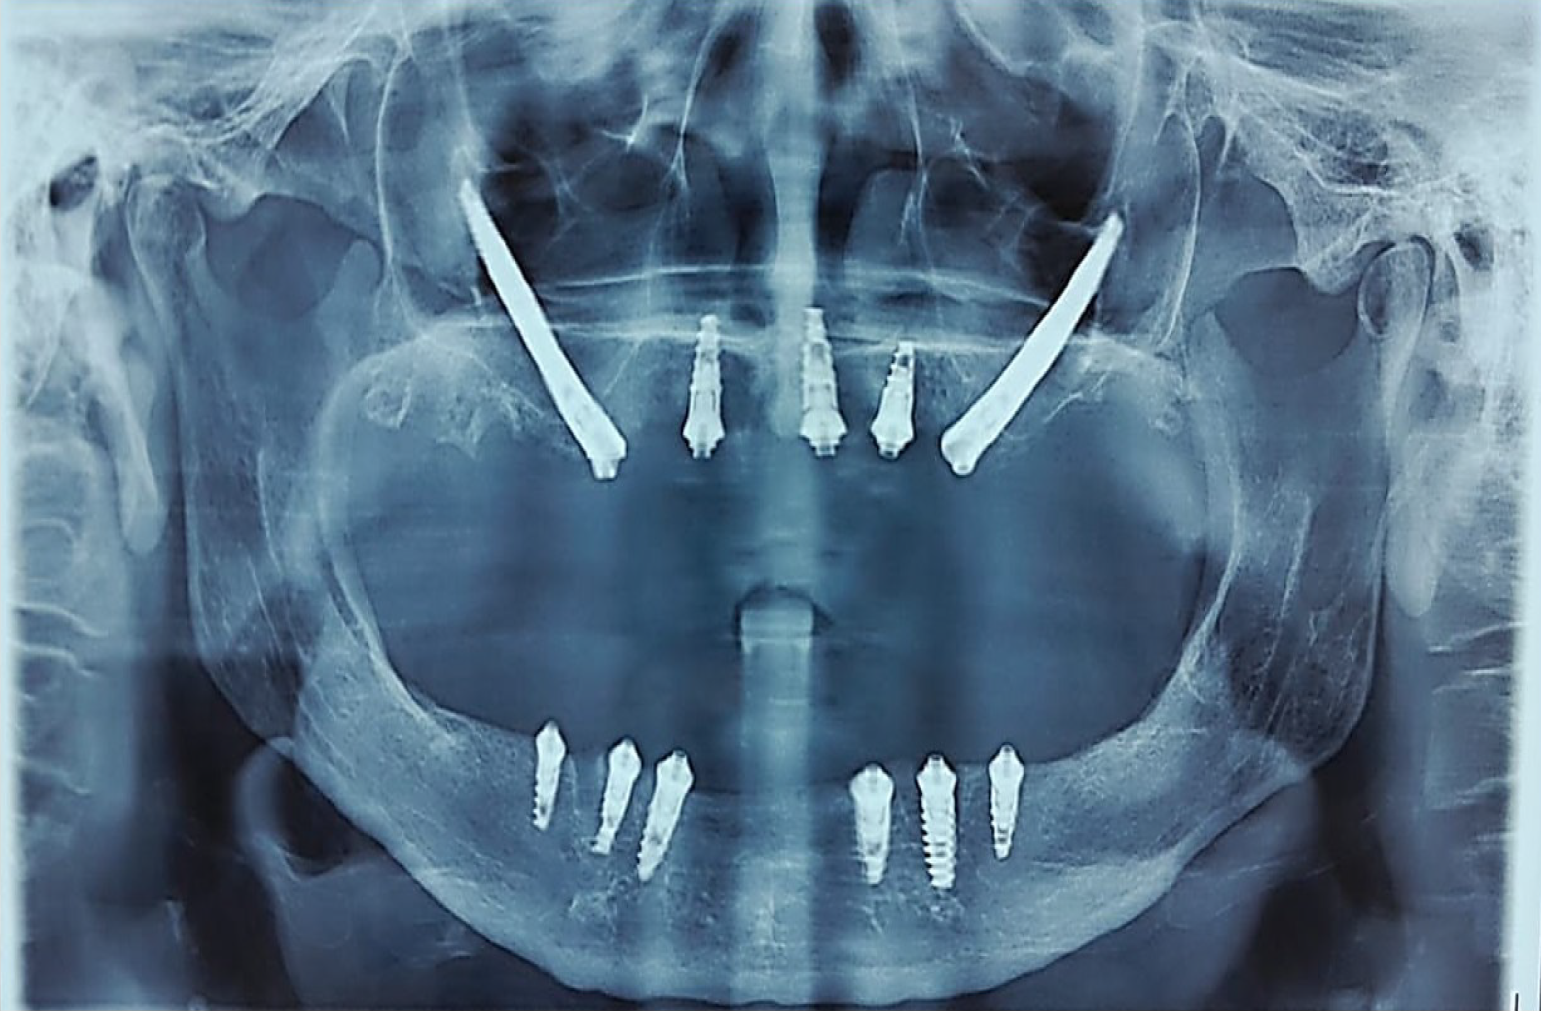

This combined implant configuration enabled immediate functional loading by improving load distribution and minimizing cantilever forces. A postoperative panoramic radiograph confirmed accurate bilateral placement of the zygomatic implants, visualization of nasalis implants in the anterior nasal floor region, and stable positioning of conventional mandibular implants (Figure 6).

The post-prosthetic panoramic radiograph confirmed stable fixation of the hybrid prosthesis to the supporting implants, demonstrating accurate seating of the metal framework and appropriate implant-abutment connections (Figure 9A). Radiographic evaluation showed maintained peri-implant bone levels, with no evidence of early marginal bone loss, framework misfit, or mechanical complications. Comparative radiographic assessment between immediate postoperative and 6-month follow-up images revealed no clinically significant crestal bone level changes around the zygomatic or nasalis implants. Marginal bone levels were evaluated using panoramic radiographs and CBCT images by measuring the distance from the implant platform to the first bone-implant contact.